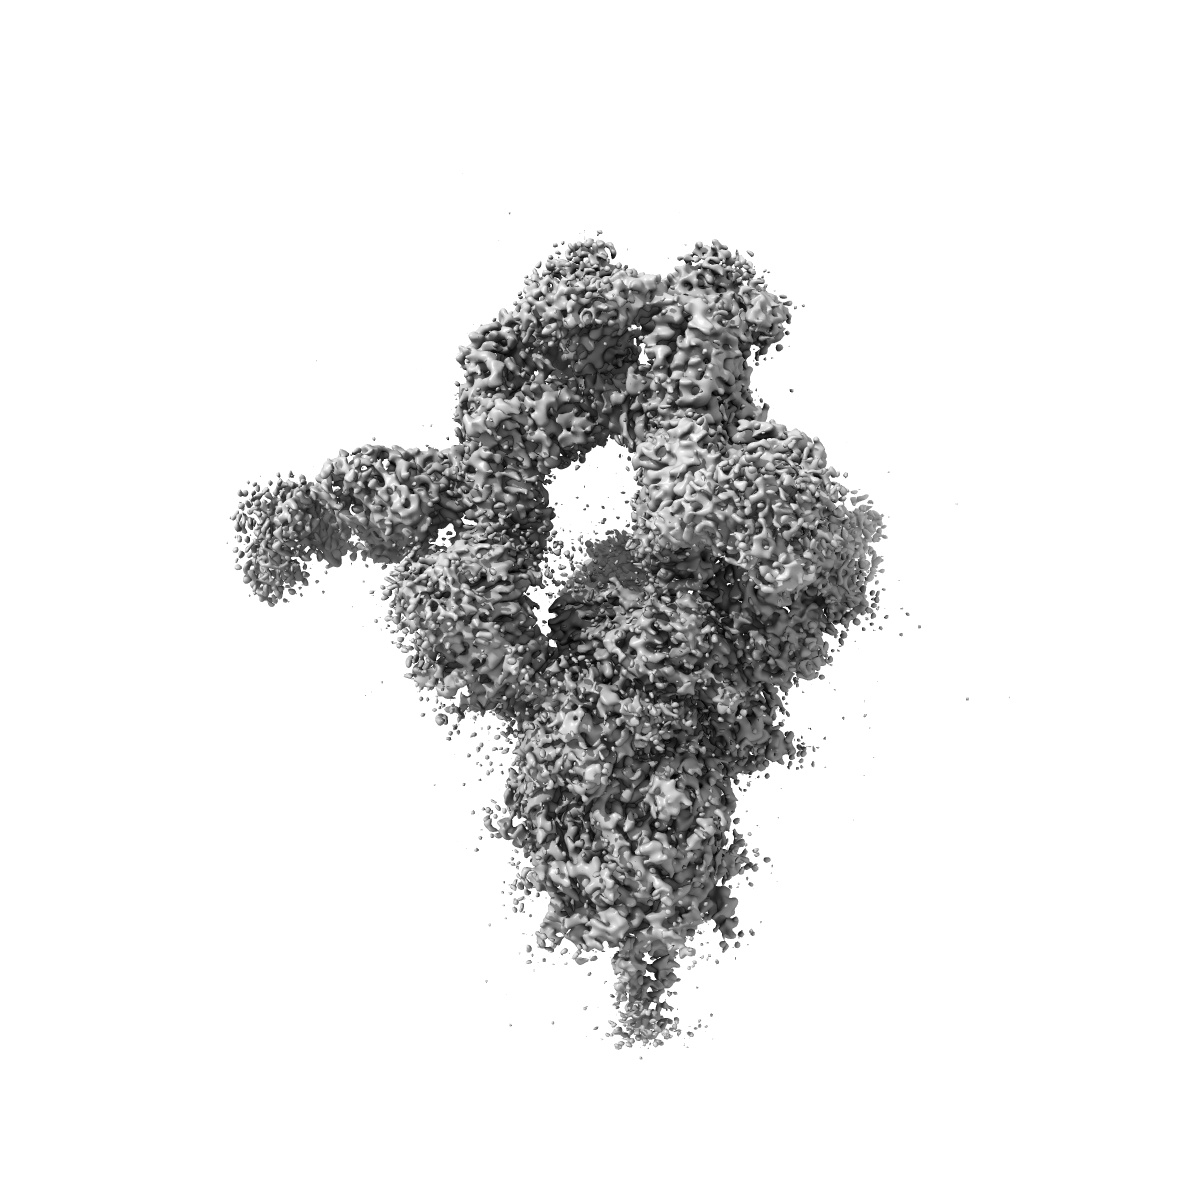

Cryo-EM structure of SARS-CoV-2 Delta Spike protein in complex with BA7208 and BA7125 fab

Single-particle3.08 Å

Sample: Cryo-EM structure of SARS-CoV-2 Delta Spike protein in complex with BA7208 and BA7125 fab